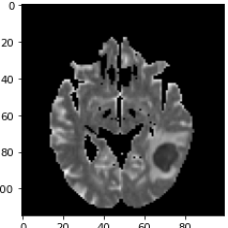

As a first example, we consider a neuroradiological application, where we aim for dividing MRI images showing an abscess into the regions healthy, abscess and edema. The left column in Fig. 6 shows three channels of an MRI dataset using diffusion weighted imaging (DWI), apparent diffusion coefficient (ADC), and T2 sequence. As preprocessing, the ADC maps and T2 images were windowed and standardized to have intensity values between . The second column shows the segmentations obtained by MMCV. Here we chose a weighted linear combination of the three images as the input image. This strategy was found to provide better results than treating the three images as separate channels. We selected the regularization parameter empirically so that it led to the best results. The remaining columns of Fig. 6 show the segmentation masks corresponding to four different regularization parameters. Smaller values of result in quite inaccurate results containing many false positives. The results in the last row, which were obtained by setting the regularization parameter to , show an improvement compared to the ones in the previous columns. Quantitative evaluation metrics are summarized in Table 3.